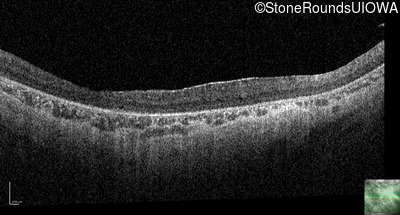

Optical Coherence Tomography - Right - 10/300 sc

Exemplar / OCT Stack